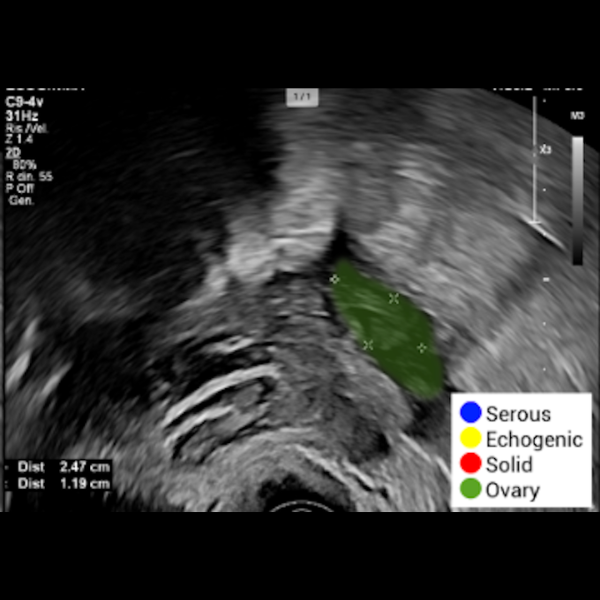

OvAi Focus utilizza algoritmi di AI addestrati per supportare la descrizione oggettiva delle strutture anatomiche, integrandosi nel flusso di lavoro senza interruzioni. Il software analizza l’imaging, identificando ed evidenziando l’organo e le strutture funzionali attraverso la definizione dei profili anatomici.

- Individua le aree solide e liquide della massa tramite codifica in falsi colori.

- Discrimina tra componenti anecogene, sierose e zone iperecogene

- Calcola il rapporto tra area solida e area totale (criteri IOTA) per una refertazione oggettiva.